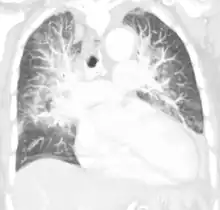

| Pulmonary edema with small pleural effusions on both sides | |

Low oxygen saturation in blood and disturbed arterial blood gas readings support the proposed diagnosis by suggesting a pulmonary shunt. A chest X-ray will show fluid in the alveolar walls, Kerley B lines, increased vascular shadowing in a classical batwing peri-hilum pattern, upper lobe diversion (biased blood flow to the superior parts instead of inferior parts of the lung), and possibly pleural effusions. In contrast, patchy alveolar infiltrates are more typically associated with noncardiogenic edema[3]